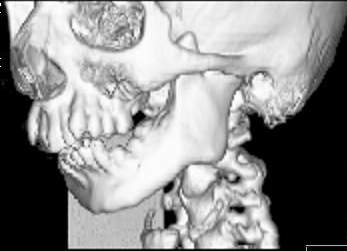

Пациент В., 13 лет. Диагноз: Костный анкилоз левого височно-нижнечелюстного сустава (ВНЧС), левосторонняя микрогения. Болеет с 2-х летнего возраста. Возможная причина развития анкилоза – воспалительный процесс (в первые 1,5 года жизни часто болел простудными заболеваниями, травму родители отрицают). В 3 и 5 лет проводилась редрессация – безуспешно.Прилагаются: ортопантомограмма, кадры СКТ с 3Д реконструкцией. Вопросы: определение тактики лечения – вид и сроки реконструктивно-пластической операции (этапов операции), а именно – неоартропластики и устранения микрогении, медикаментозная терапия в до- и послеоперационный период, ортодонтическое лечение.